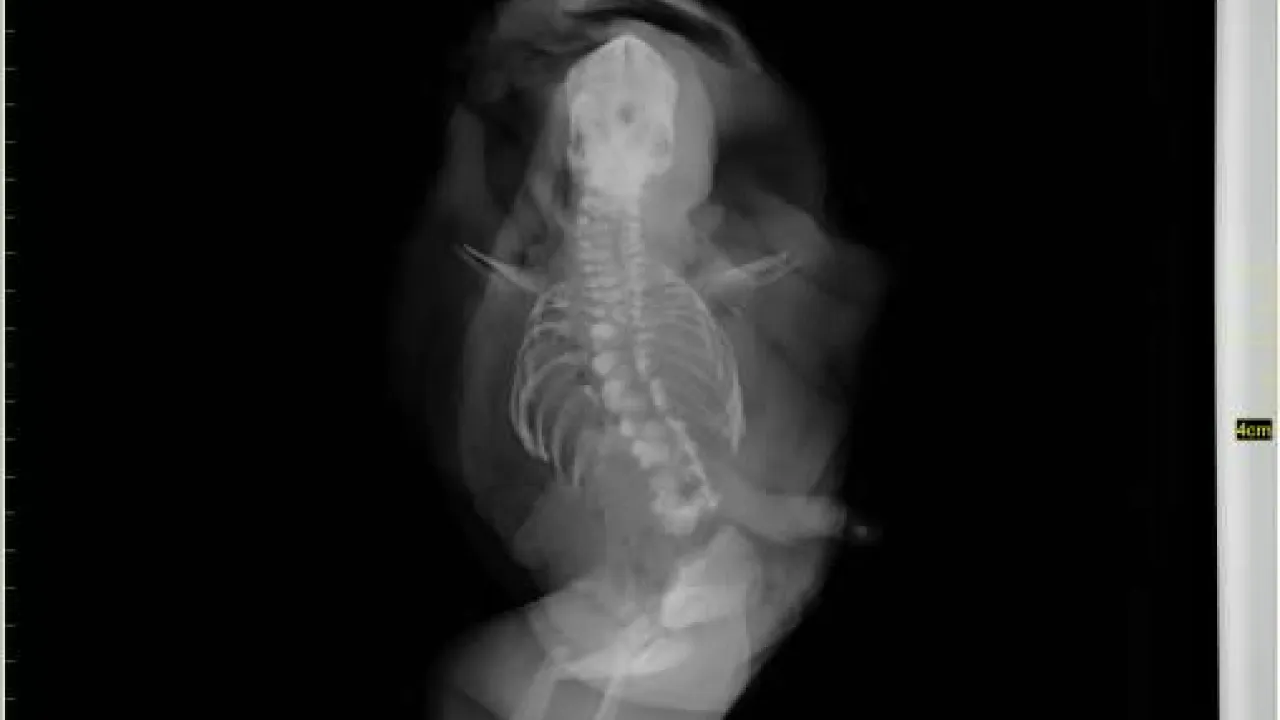

Skeleton and body morphology, Twin reversed arterial profusion sequence

Skeleton, Twin reversed arterial profusion sequence